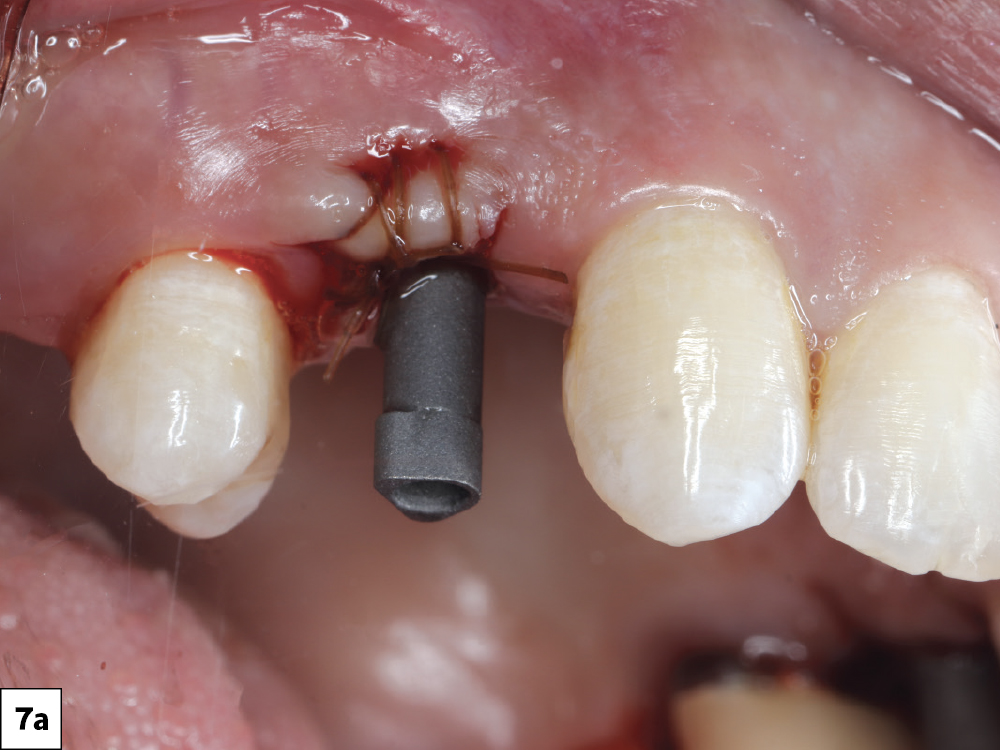

Immediately after placement, scan bodies were threaded in place, and the surgical field was scanned

Figures 7a, 7b: Immediately after placement, scan bodies were threaded in place, and the surgical field was scanned. The scans were imported directly into the fastdesign.io Software and Design Station, the CAD platform that communicates seamlessly with the fastmill.ioIn-Office Mill.